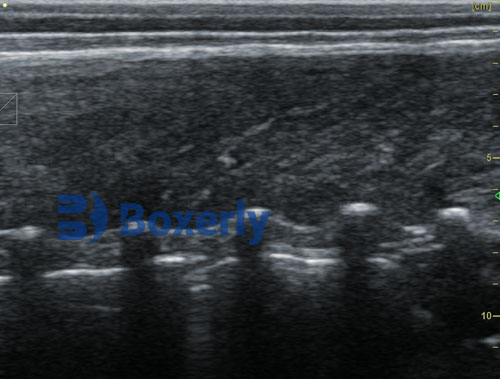

DZ20 measures pig back fat thickness and eye muscle area(1)

DZ20 measures pig back fat thickness and eye muscle area(2)